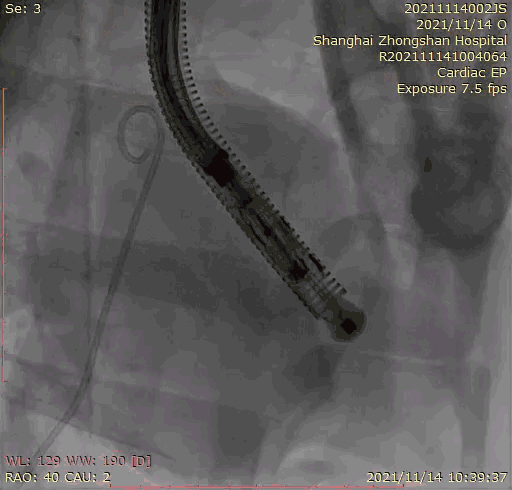

本次臨床前研究經右側頸靜脈置入LuX-Valve Plus輸送系統可調彎鞘管,在DSA及超聲引導下將人工三尖瓣瓣膜植入到原有三尖瓣位置,利用獨特的錨定技術將人工瓣膜支架可靠固定在預定的位置。